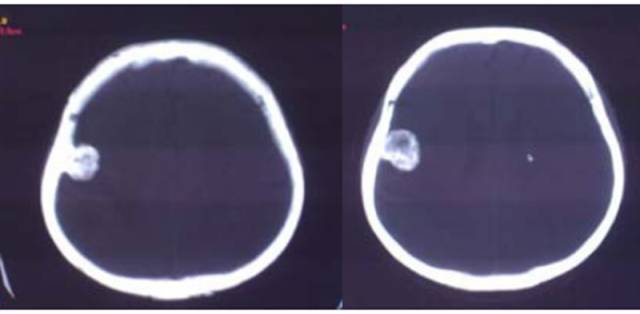

病例:男性,30岁,头痛2月

CT平扫